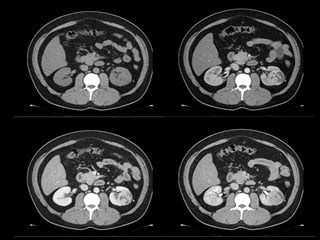

INSTALACIÓN DE DRENAJE PERCUTANEO